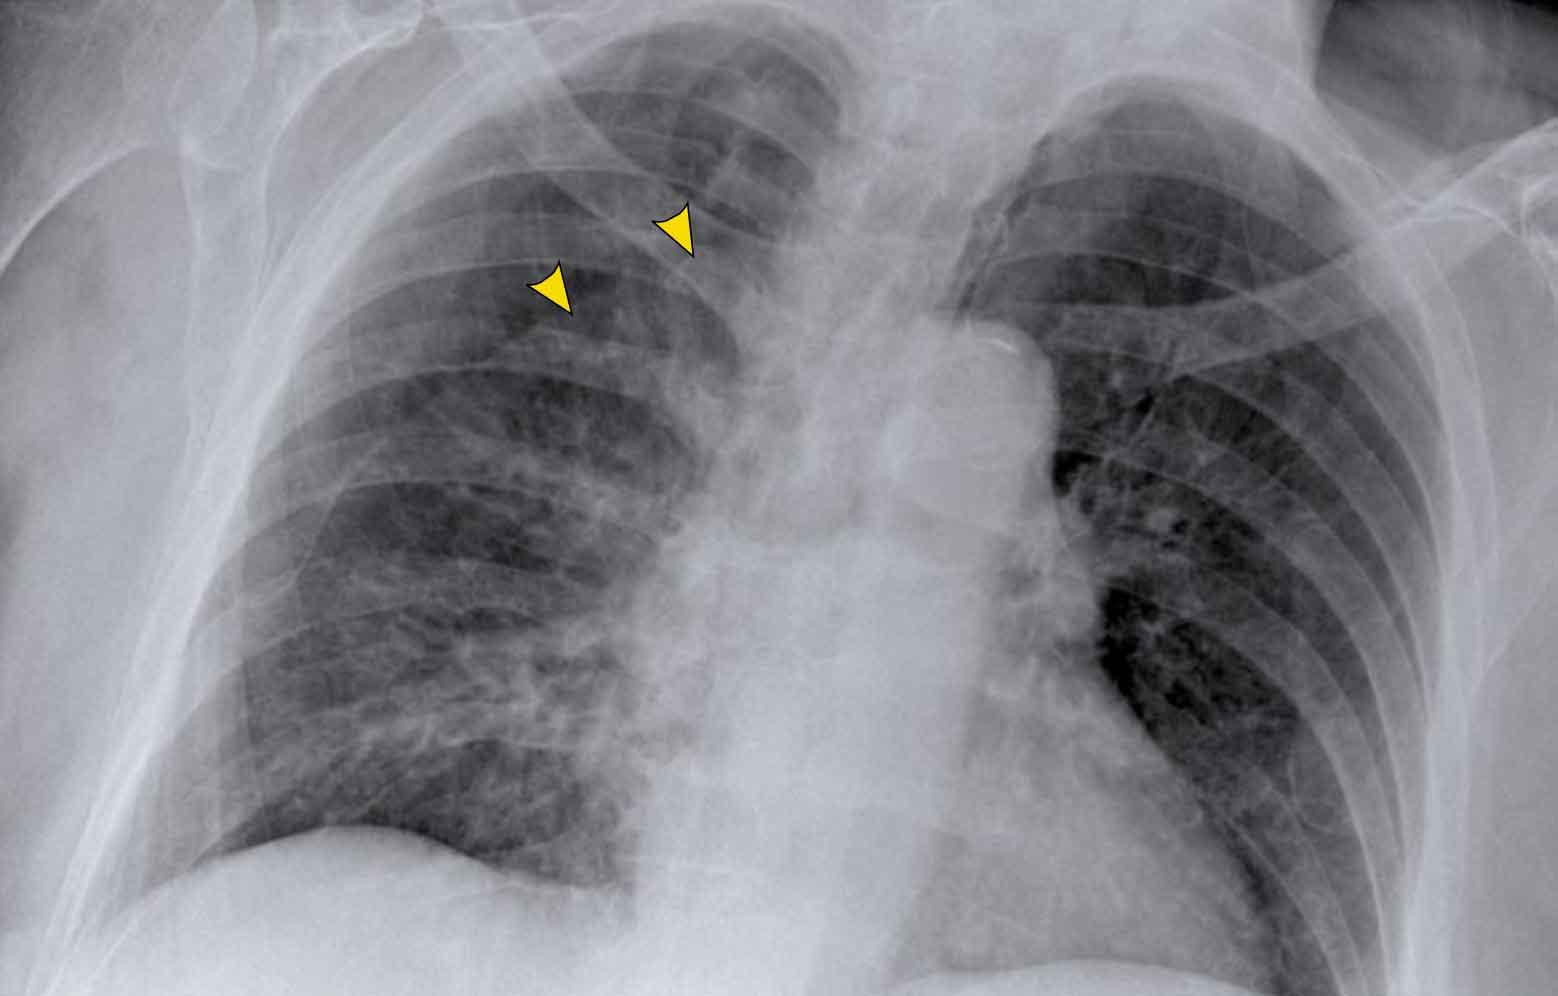

To rốn phổi – ca 1

Trong trường hợp này, bóng rốn phổi to ra ở cả hai bên. Nguyên nhân có thể do mạch máu giãn to hoặc hạch bạch huyết to. Một dấu hiệu rất có giá trị trong trường hợp này là khối nằm bên phải khí quản.

Đây được gọi là dấu hiệu 1-2-3 trong bệnh sarcoidosis, tức là to rốn phổi trái, rốn phổi phải và hạch cạnh khí quản.

Dưới đây là thêm một số ví dụ về bệnh sarcoidosis.

Nhấp vào hình để phóng to.

- Hạch bạch huyết to và hình ảnh kính mờ (ground-glass) ở phổi

- Hạch bạch huyết to, dấu hiệu 1-2-3

- Hạch bạch huyết to khối lớn

- Dấu hiệu 1-2-3

- Hình ảnh nốt ở phổi, không có hạch bạch huyết to

- Hạch bạch huyết rốn phổi và cạnh khí quản to